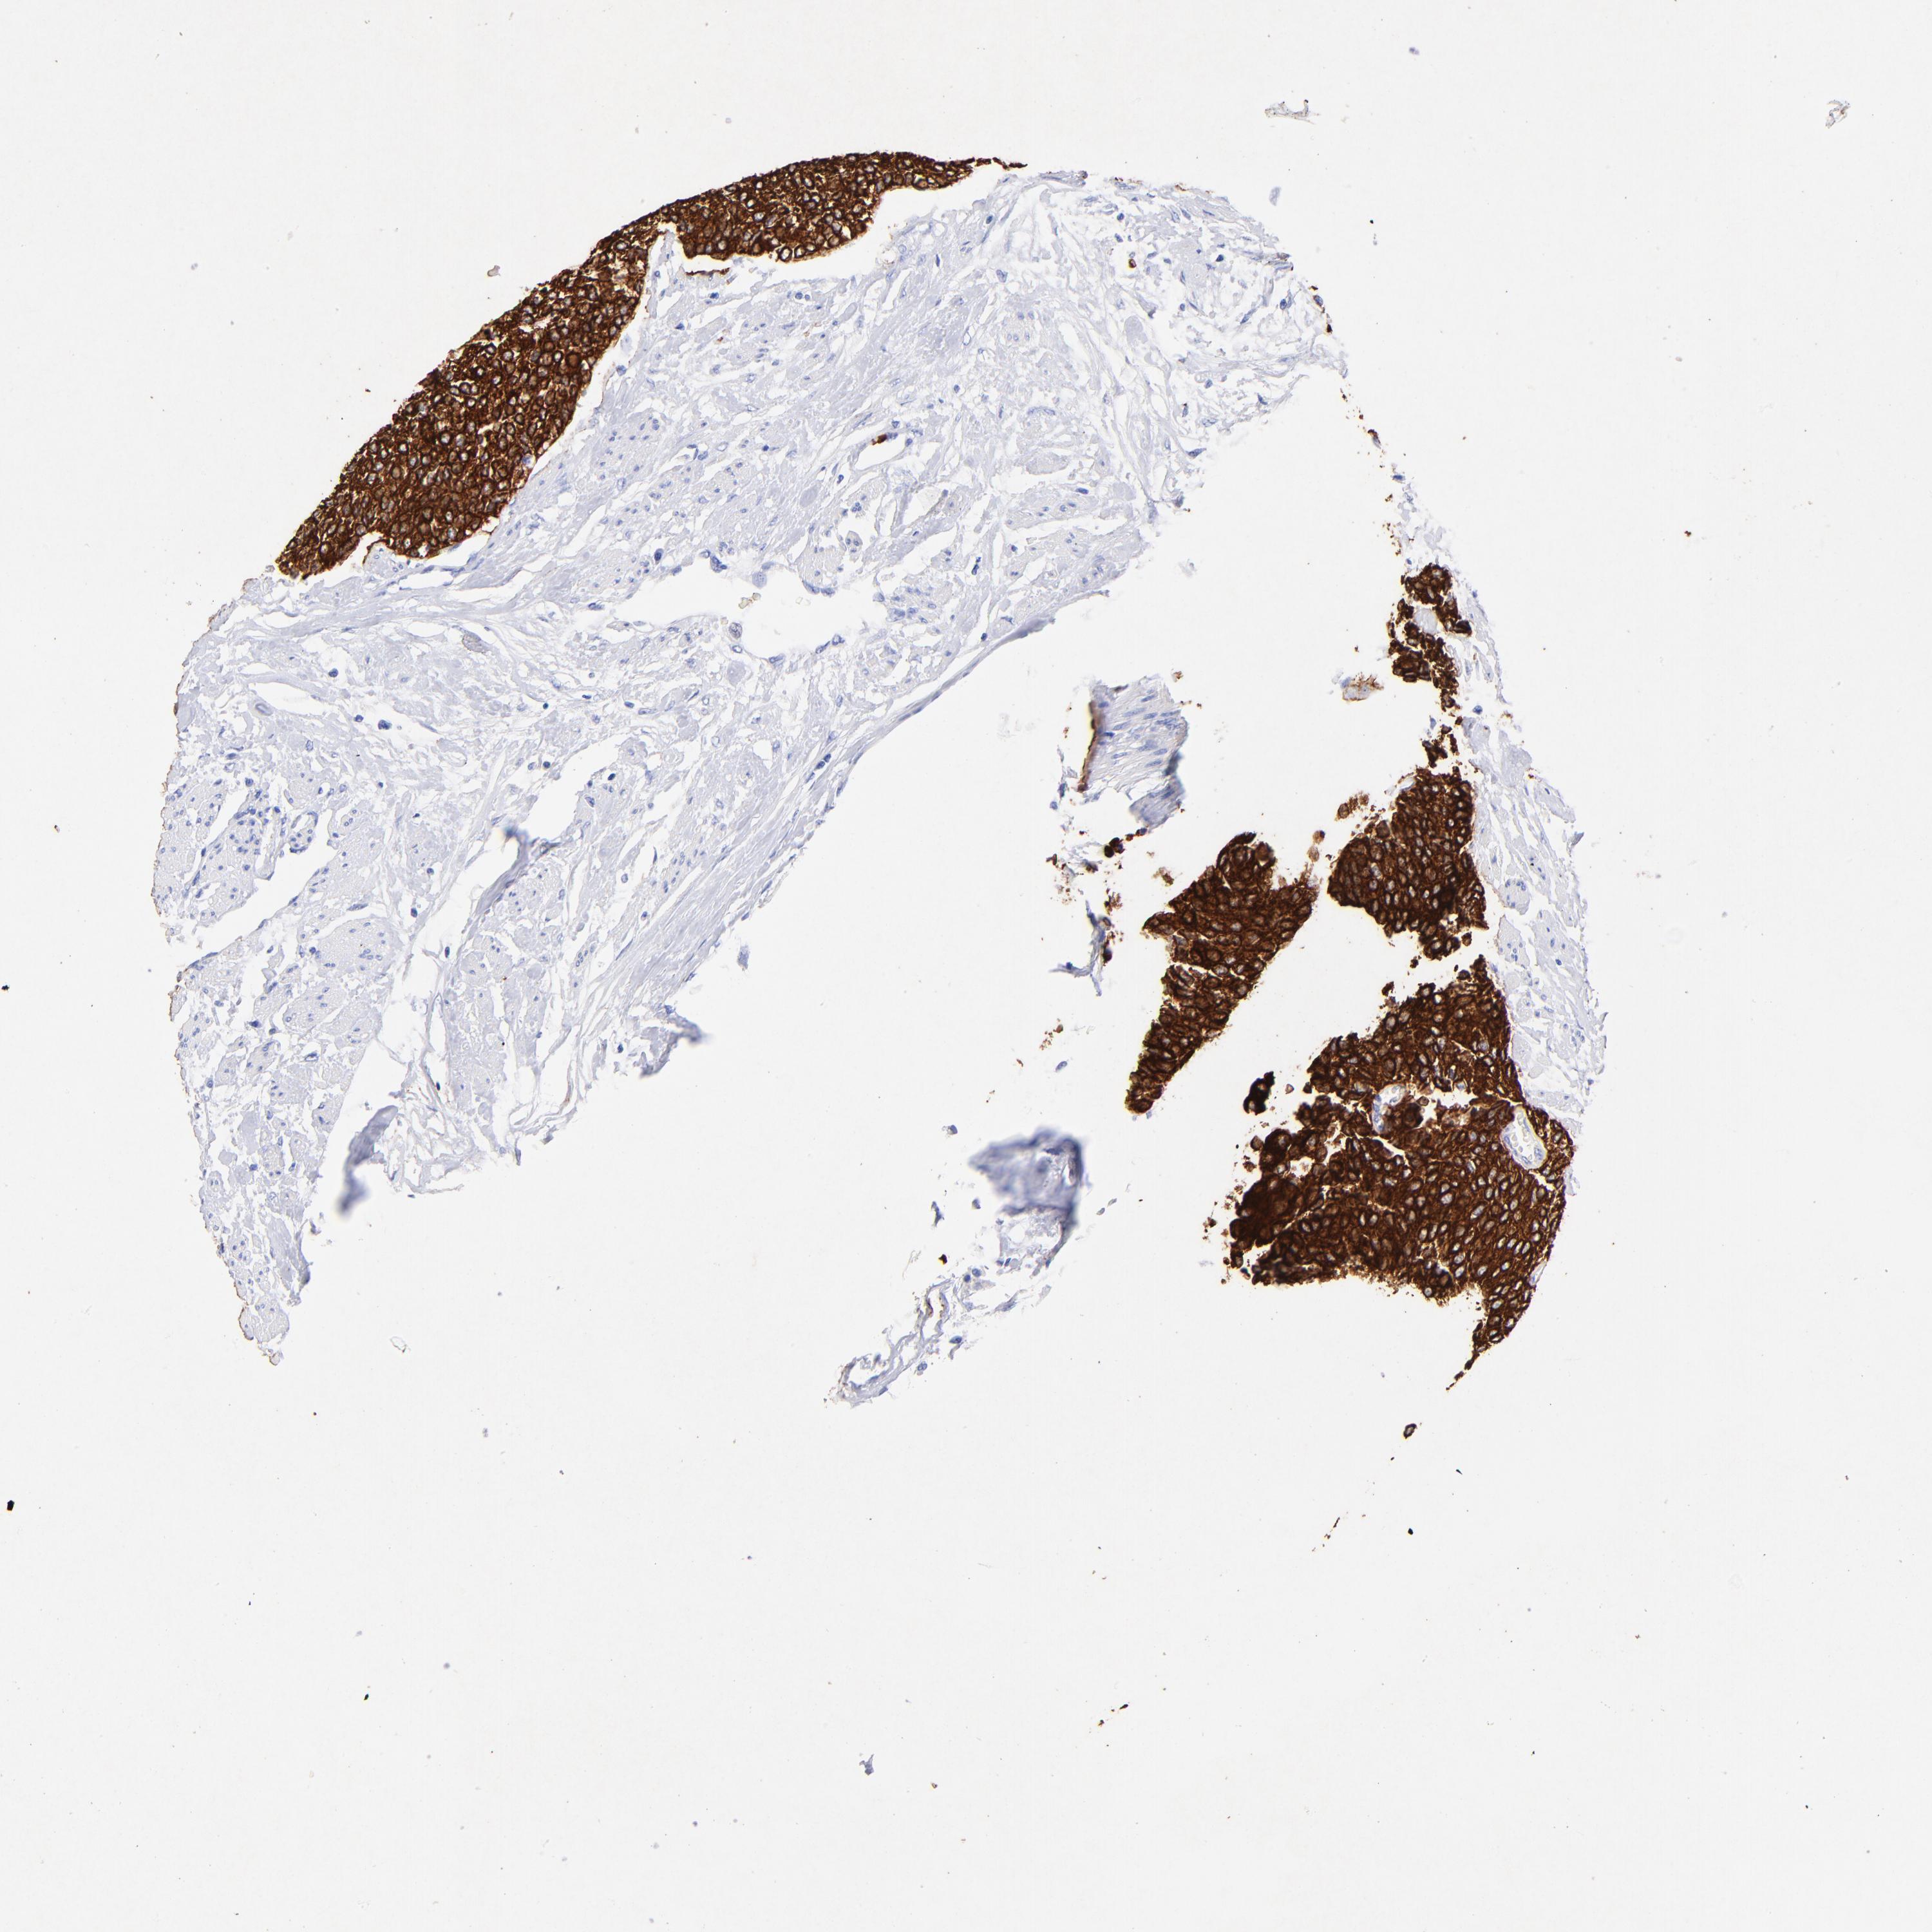

UROTHELIAL CANCER - Protein expressioni

A mouse-over function shows sample information and annotation data. Click on an image to view it in a full screen mode. Samples can be filtered based on level of antibody staining by selecting one or several of the following categories: high, medium, low and not detected. The assay and annotation is described here.

Antibody stainingi

Antibody staining in the annotated cell types in the current human tissue is reported as not detected, low, medium, or high, based on conventional immunohistochemistry profiling in selected tissues. This score is based on the combination of the staining intensity and fraction of stained cells.

Each image is clickable and will lead to virtual microscopy that enables deeper exploration of all samples and also displays staining intensity scores, fraction scores and subcellular localization as well as patient and tissue information for each sample.

Antibody HPA002465

Antibody CAB000031

Staining

High

Medium

Low

Not detected

Intensity

Strong

Moderate

Weak

Negative

Quantity

>75%

75%-25%

<25%

None

Location

Nuclear

Cytoplasmic/membranous

Cytoplasmic/membranous,nuclear

Urothelial carcinoma, High grade

Urothelial carcinoma, Low grade

Adenocarcinoma, NOS